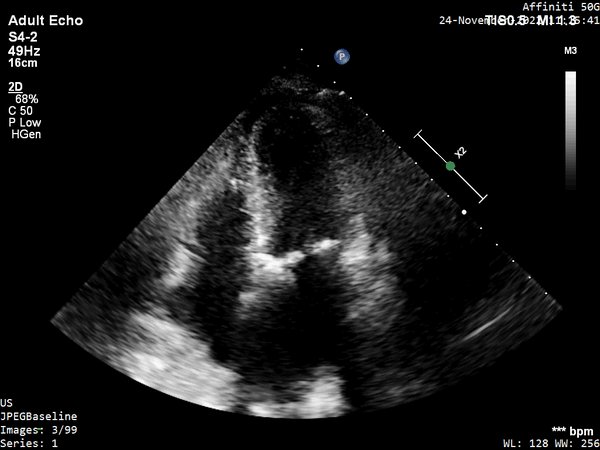

A4C

4/ A4C w/ colour